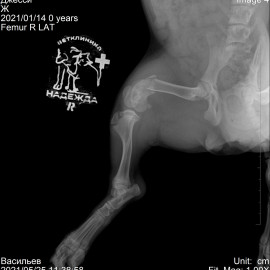

Обратились в нашу клинику из города Боровичи с щенком Джек-Рассел-Терьера по кличке Джесси. Щенка сбил велосипед, после чего она перестала наступать на правую заднюю лапу. После рентгенологического исследования был поставлен диагноз - перелом правого бедра. Проведена операция: остеосинтез правого бедра.

Снимок 1 до операции.